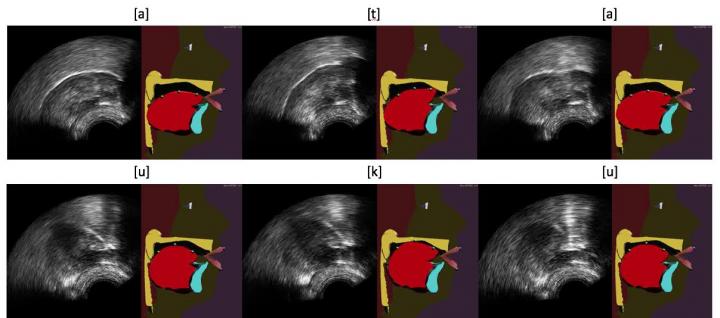

A team of researchers in the GIPSA-Lab (CNRS/Université Grenoble Alpes/Grenoble INP) and at INRIA Grenoble Rhône-Alpes has developed a system that can display the movements of our own tongues in real time. Captured using an ultrasound probe placed under the jaw, these movements are processed by a machine learning algorithm that controls an "articulatory talking head." As well as the face and lips, this avatar shows the tongue, palate and teeth, which are usually hidden inside the vocal tract. This "visual biofeedback" system, which ought to be easier to understand and therefore should produce better correction of pronunciation, could be used for speech therapy and for learning foreign languages. This work is published in the October 2017 issue of Speech Communication .

For several years, researchers have been using ultrasound to design biofeedback systems. The image of the tongue is obtained by placing under the jaw a probe similar to that used conventionally to look at a heart or fetus. This image is sometimes deemed to be difficult for a patient to use because it is not very good quality and does not provide any information on the location of the palate and teeth. In this new work, the present team of researchers propose to improve this visual feedback by automatically animating an articulatory talking head in real time from ultrasound images. This virtual clone of a real speaker, in development for many years at the GIPSA-Lab, produces a contextualized -- and therefore more natural -- visualization of articulatory movements.